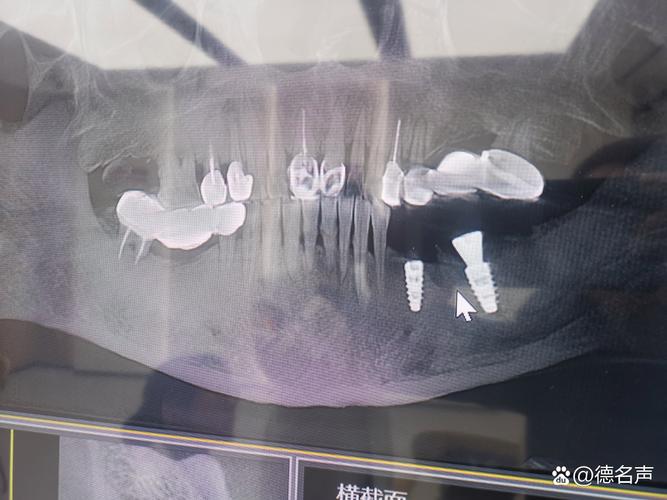

- 骨量评估:准确测量牙槽骨的高度、厚度和长度,判断是否满足种植体植入的最低要求(通常种植体长度需8-10mm,直径3.5-5mm,骨厚度需至少1mm以上),若骨量不足,需提前进行植骨增量,否则可能导致种植体松动、脱落。

- 解剖结构定位:清晰显示下牙槽神经管、上颌窦、颏孔等重要解剖结构的位置与走行,下颌后牙区种植时,若种植体误入下牙槽神经管,可能造成下唇麻木等神经损伤;上颌后牙区种植时,若穿透上颌窦底,可能引发上颌窦炎,甚至导致种植体感染失败。

- 骨密度分析:骨密度直接影响种植体的初期稳定性,CBCT可通过灰度值评估骨密度(如D1-D4类骨),医生据此选择合适的种植体类型(如亲水性种植体适用于低密度骨),并调整植入扭矩,避免因骨密度过低导致种植体骨结合失败。

- 邻牙及软组织观察:了解邻牙牙根是否倾斜、有无根尖病变,以及牙龈厚度、附着龈宽度等,为种植体植入位置、角度设计提供依据,避免损伤邻牙或影响后期修复的美观与功能。